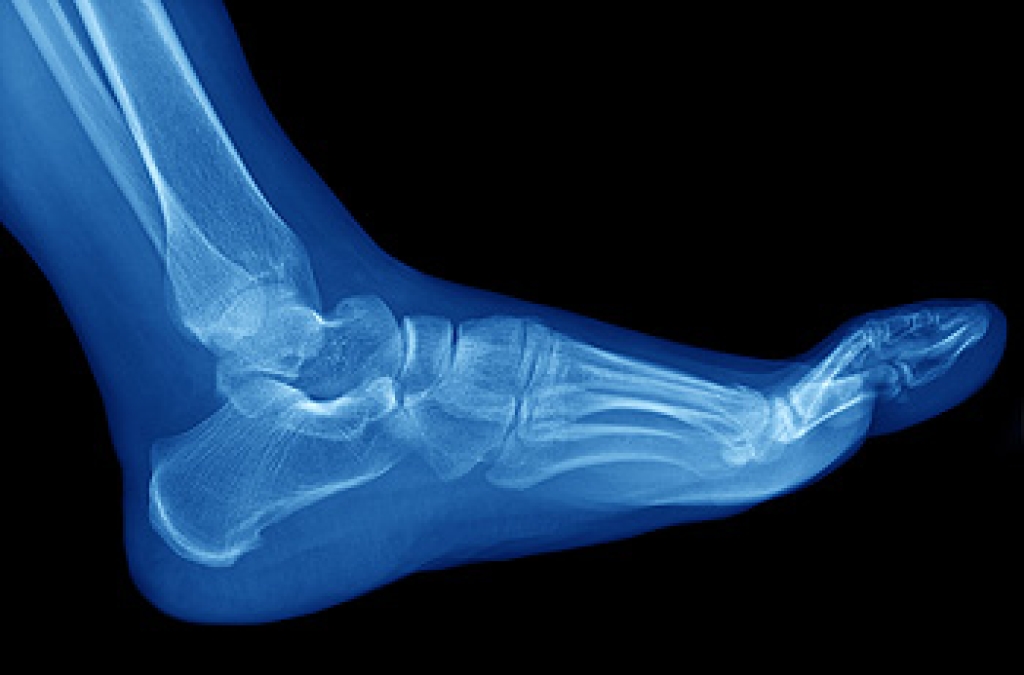

Plantar fasciitis is the inflammation of the thick band of tissue that runs along the bottom of your foot, known as the plantar fascia, and causes mild to severe heel pain.